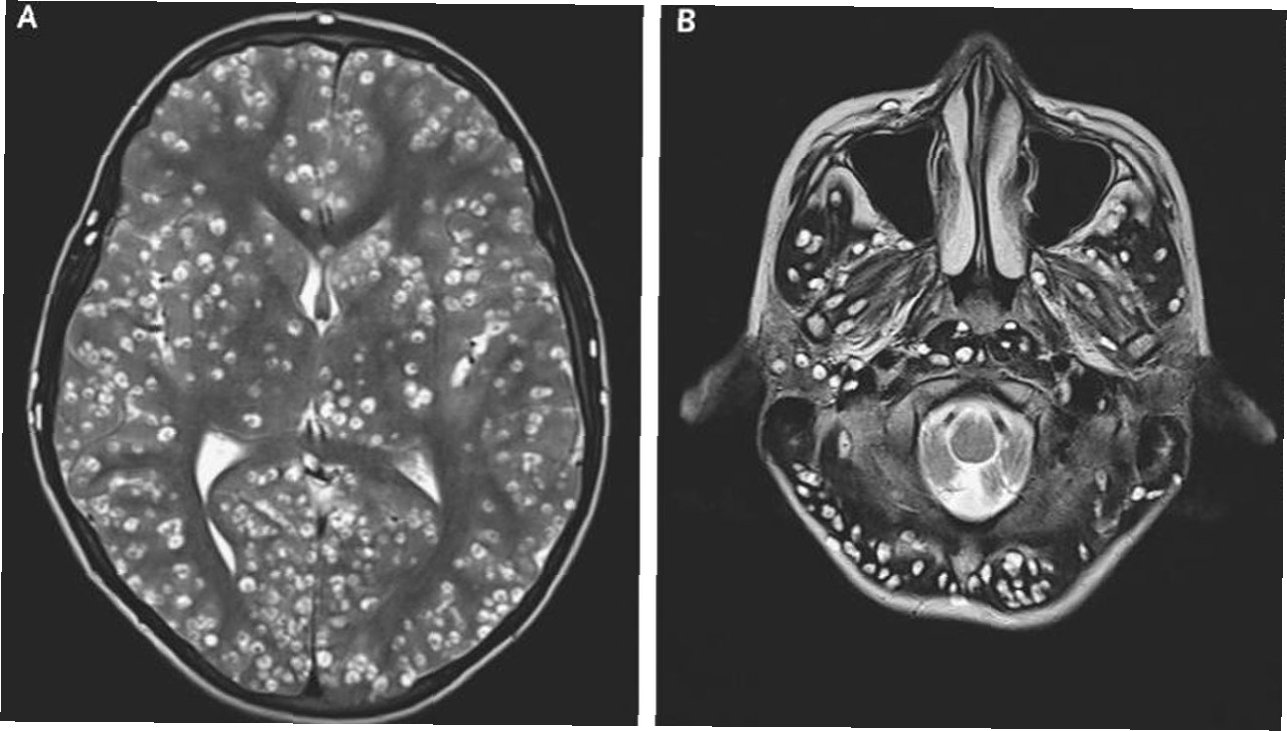

건협은 지난해 7월 발견된 희귀 사례를 공개하며, 60대 여성의 소화불량, 변비, 설사 등의 증상과 대장 내시경 검사에서 발견된 이전고환극구흡충 감염 사례를 상세히 설명했습니다. 이 기생충은 소장 말단과 대장에서 발견되는 것이 특징이며, 2014년 이후 10년 만에 국내에서 발견된 사례입니다. 또한, 20, 30대 유튜버가 아프리카 말라위 호수에서 수영 후 주혈흡충에 감염되어 소변에 피가 나오고 복통과 고열에 시달린 사례는 해외여행 시의 위험성을 경고합니다.

기생충 감염 시에는 복통, 설사, 발열, 소변에 피가 섞여 나오는 증상 등이 나타날 수 있습니다. 이러한 증상이 나타나면 즉시 병원을 방문하여 정확한 진단을 받고, 적절한 치료를 받아야 합니다. 특히, 해외여행 후 이러한 증상이 나타난다면, 여행 국가와 관련된 기생충 감염 가능성을 의료진에게 알려야 합니다. 프라지칸텔과 같은 약물 치료를 통해 완치될 수 있습니다.